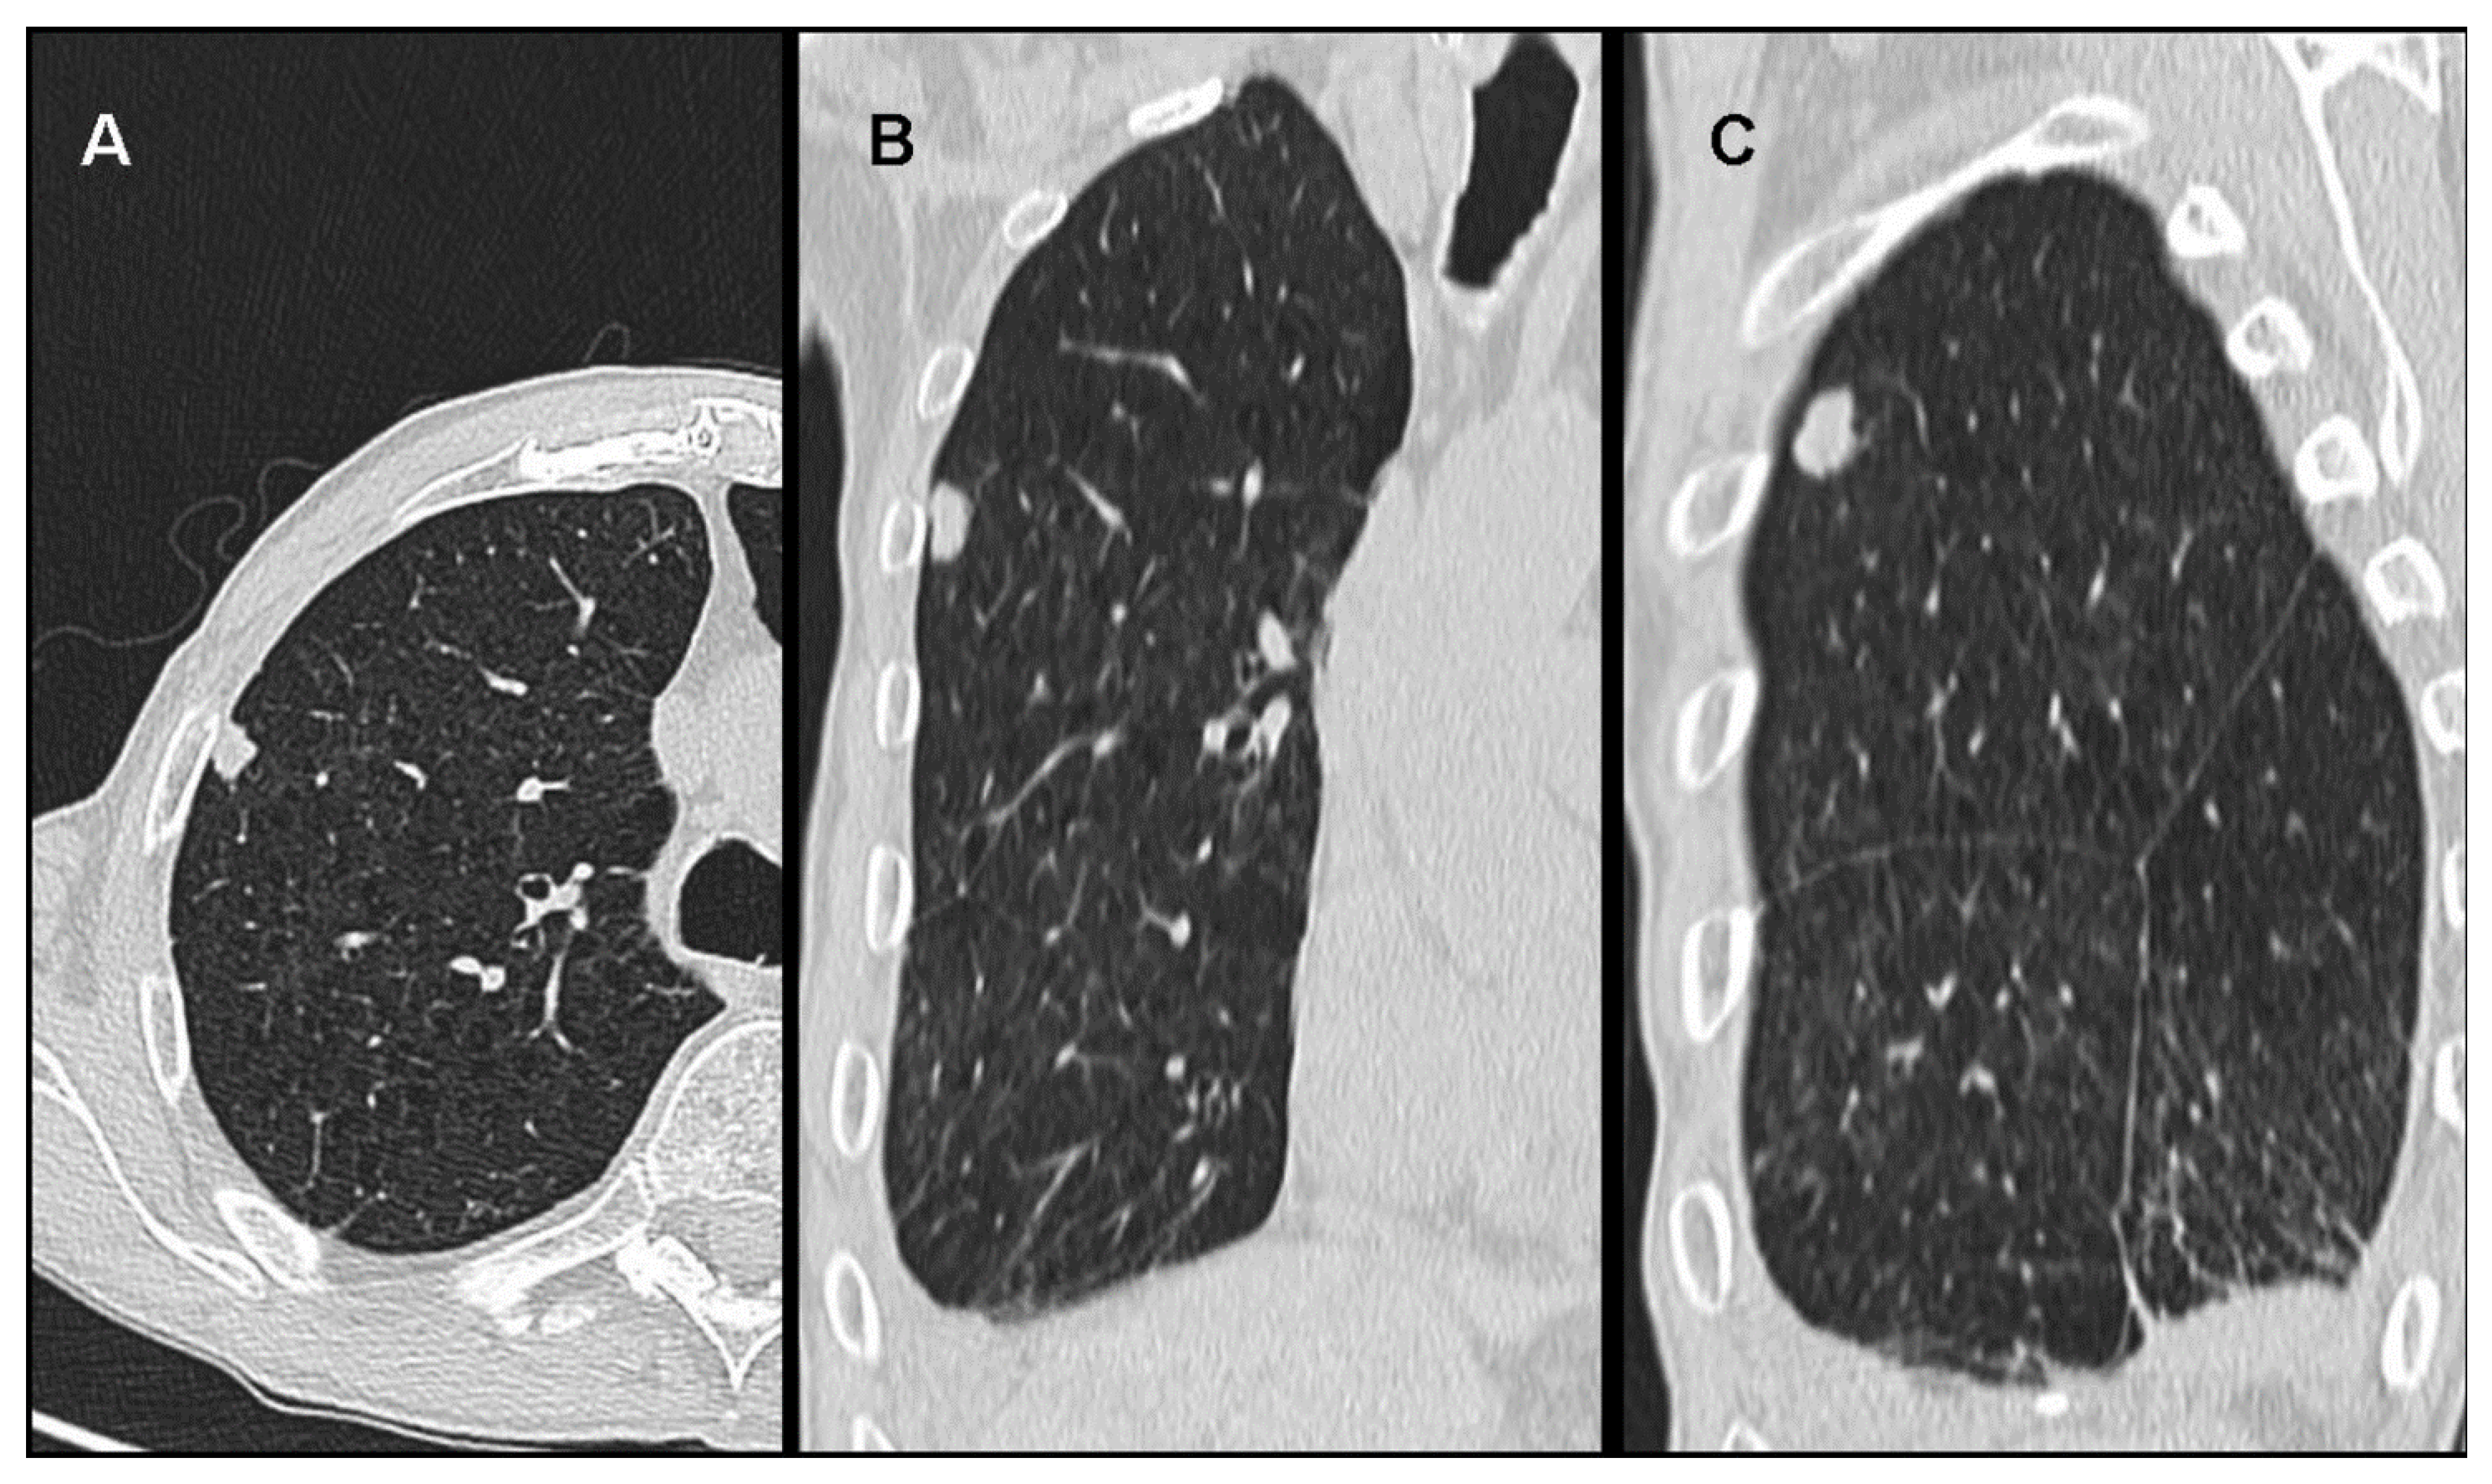

3. Unusual Radiological Presentation